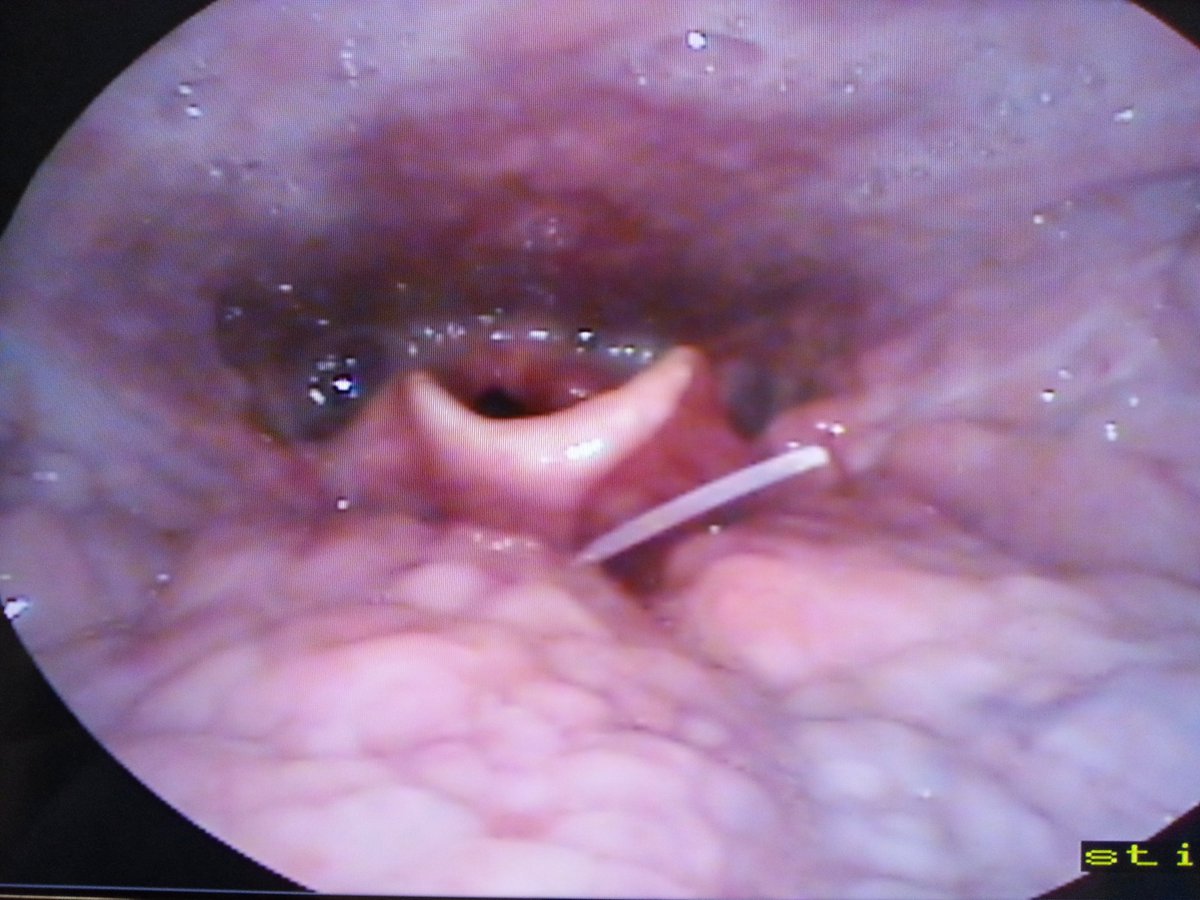

btw 漏唔一個程序: 喉鏡之後, 醫生會安排照X光, 有一定機會睇到大概位置.

但個人經驗&醫生都咁講, 因為條骨不可能太大&X光技術嘅根本問題, X光係呢件事, 都係廢嘅. 但程序係要試埋.

btw 漏唔一個程序: 喉鏡之後, 醫生會安排照X光, 有一定機會睇到大概位置.

但個人經驗&醫生都咁講, 因為條骨不可能太大&X光技術嘅根本問題, X光係呢件事, 都係廢嘅. 但程序係要試埋.

果時去急症都係呢個流程